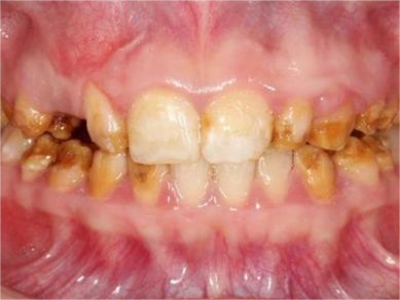

牙釉质发育不全牙齿棕色有缺损图

牙釉质发育不全患者牙齿出现明显的缺损表现,并于表面形成深褐色的蜂窝状、竖条状的凹坑,甚至形成洞,患者上下牙失去咬合能力。